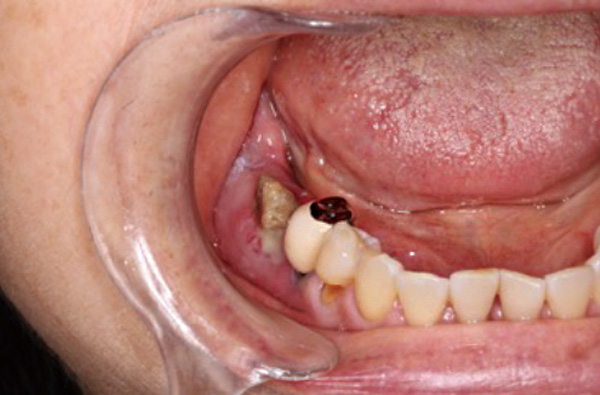

右顔面に発赤と排膿あり。

パノラマ写真で右下顎に病的骨折を認めます。(矢印)